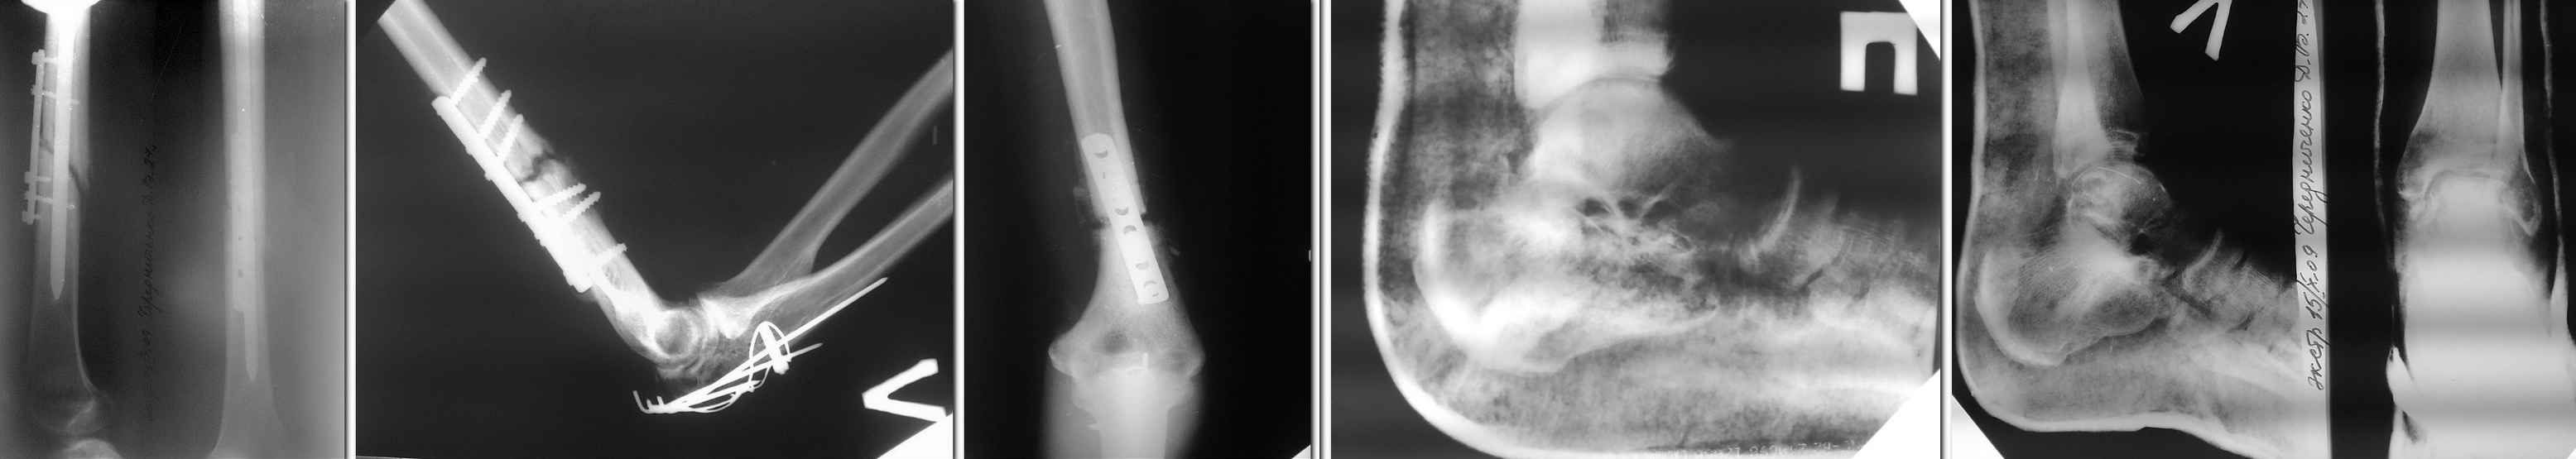

Уважаемые коллеги! Будем признательны любому совету в отношении тактики лечения пациента

Ч. 27 лет, поступившего в наше отделение для этапного лечения по поводу сочетанной травмы,

полученной 19.07.2009 в ДТП.

Оперирован в другом лечебном учреждение 05.08.09- остеосинтез левой бедренной кости,

левой плечевой кости, левого локтевого отростка, трансартикулярная фиксация спицами

левой таранной кости, выполнена закрытая репозиция перелома правой пяточной кости

гипсовым лангетом. В настоящее время признаки консолидации левой бедренной и левой

плечевой костей выражены слабо, имеются контрактуры левых локтевого и коленного суставов,

спицы удалены продолжается иммобилизация стоп. Мнения коллег по дальнейшей тактике

лечения разошлись: - выполнить реостеосинтез бедренной и плечевой костей; - продолжать

консервативное лечение в надежде на консолидацию переломов, поскольку оперативное

пособие не приведёт к более ранней активизации больного из-за имеющихся переломов костей

стоп и верхней конечности. Заранее спасибо.